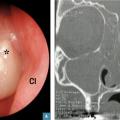

Avec polypes (figure)

Les glucocorticoïdes nasaux, par rapport au placebo, diminuent significativement les symptômes, la taille des polypes, le risque de récidive, et augmentent le débit inspiratoire nasal maximal, qu’ils soient de nouvelle (mométasone, fluticasone) ou de première génération (budénoside, béclométasone, triamcinolone). La réduction de volume des polypes est d’autant plus importante s’ils siègent dans une cavité nasale opérée.